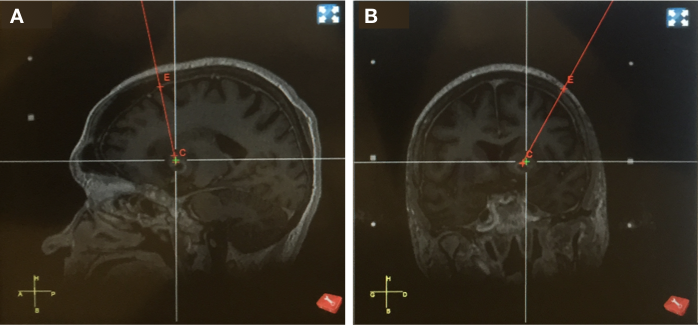

如今,在手术过程中,医务人员仍需同时操作不同的定位和成像系统。例如,针对难以触及的脑深部肿瘤,需要一种能够实时跟踪毫米级设备的系统,以精确引导其到达手术部位。此外,原本已十分复杂的医疗环境要求定位系统必须“易于使用”,即具备侵入性小、可重复性强以及适用于患者的特点。这一需求在神经外科应用中尤为突出,这些应用结合了追踪手段与外科技术,以实现新型疗法的递送:深部脑刺激(DBS)(哈里兹等人,2013);基因治疗或细胞移植(霍凯米勒等人,2016);肿瘤改良切除术及针对肿瘤的局部药物递送(Sanai和Berger,2008)。图32展示了当前和未来神经外科应用的性能需求。

此外,减少侵入性的需求既源于降低患者副作用(由麻醉和开颅引起)的愿望,也源于对精度的要求。侵入性通过影响配准20步骤,限制了可达到的精度。事实上,开颅会导致脑脊液泄漏,从而引发脑移位(可能达到数厘米),使从术前成像技术获得的目标手术部位产生偏差。减少侵入性可通过缩小开颅尺寸甚至不开颅来实现,但这会引入需要穿透的颅骨层。该颅骨层增加了信号路径的深度和衰减,直接影响定位系统的性能(图18)。因此,研究位置精度与侵入性之间的关系有助于阐明精度要求与对身体影响之间的联系(图35)。一种全局仿射相关性似乎显现出来:随着精度提高,侵入性降低(显微镜和超快多普勒断层扫描除外,它们使用颅窗工作)。事实上,目前最精确的系统采用了更小的嵌入式元件,直接促进了非侵入性。此外,图表中出现的唯一非侵入式系统(计算机断层扫描和磁共振成像)也是目前在全球应用最广泛的系统,这表明了侵入性在现代医学中的重要性。